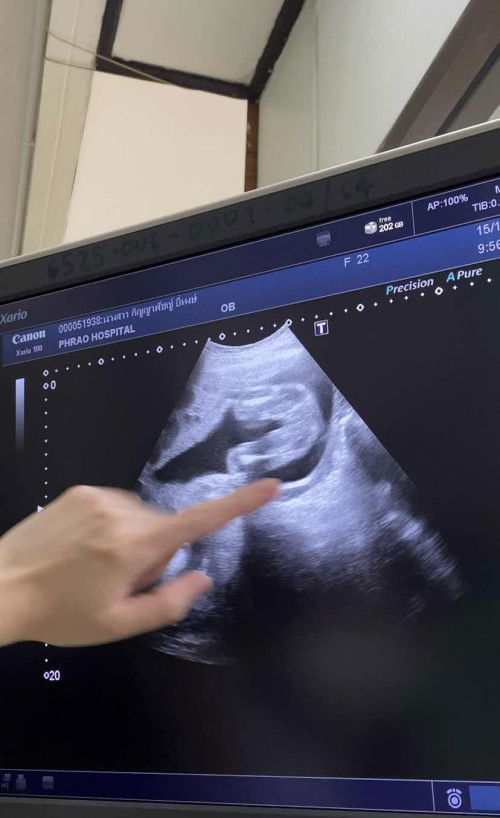

เพศหญิง100%ไหมคะแม่ๆ

อยากชัวร์จากแม่ๆหลายๆท่านค่ะว่าหญิง100%มั้ยย หมอแจ้งเพศหญิง ฝันก็ฝันว่าได้ผู้หญิงค่ะแม่ๆ🤣